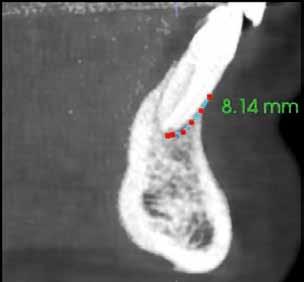

A radiológiai felvételek elemzése során a fog gyökércsúcsának megfelelően radiolucens elváltozást észleltünk, valamint a fognyak területének megfelelően szintén egy radiolucens területet figyelhettünk meg (1–2. ábra). Az elváltozások kiterjedésének és mélységének pontosabb meghatározása érdekében CBCT-felvétel készült (3. ábra). A felvétel alapján Heithersay-féle III. osztályú külső fognyaki gyökérfelszívódást diagnosztizáltunk (Heithersay Class III external cervical invasive root resorption; ECIR). Ezzel egyidejűleg pedig szimptomatikus periapikális periodontitis is fennállt. Ezt követően a pácienst a vizsgálati eredményekről, a kezelési alternatívákról és a várható prognózisról is tájékoztattuk.

A CBCT-felvételek rendkívül hasznos információkkal szolgálhatnak az endodonciai kezelések során. A felvételek segítségével meghatározhatjuk a külső fognyaki rezorptív lézió kiterjedését, felismerhetjük és osztályba sorolhatjuk az esetleges periapikális elváltozásokat, valamint nagyobb pontossággal felmérhetjük a fog belső anatómiai felépítését. Több szerző egymástól függetlenül is igazolta, hogy a CBCT rendkívül hasznos eszköz a rezorptív léziók diagnosztizálása során.

3. a–d ábra: A koronális síkú metszeten jól megfigyelhető a lézió mesio-distalis kiterjedése (a), a szaggitális síkú metszet a lézió vesztibulo-orális nagyságát mutatja (b), a gyökércsúcs körül elhelyezkedő lézió a 3 dimenziós rekonstrukciós képen és a mesio-disztális irányú metszeten is jól megfigyelhető (c–d).

A cikkekben bemutatott esetnél a kezelésre szoruló fog gyökércsúcsánál periapikális lézió volt megfigyelhető és ezzel egyidejűleg külső fognyaki gyökérrezorpció is fennállt. A periapikális és a rezorptív lézió méretének pontos meghatározását és térbeli elhelyezkedésének vizsgálatát CBCT-felvétel segítségével végeztük.